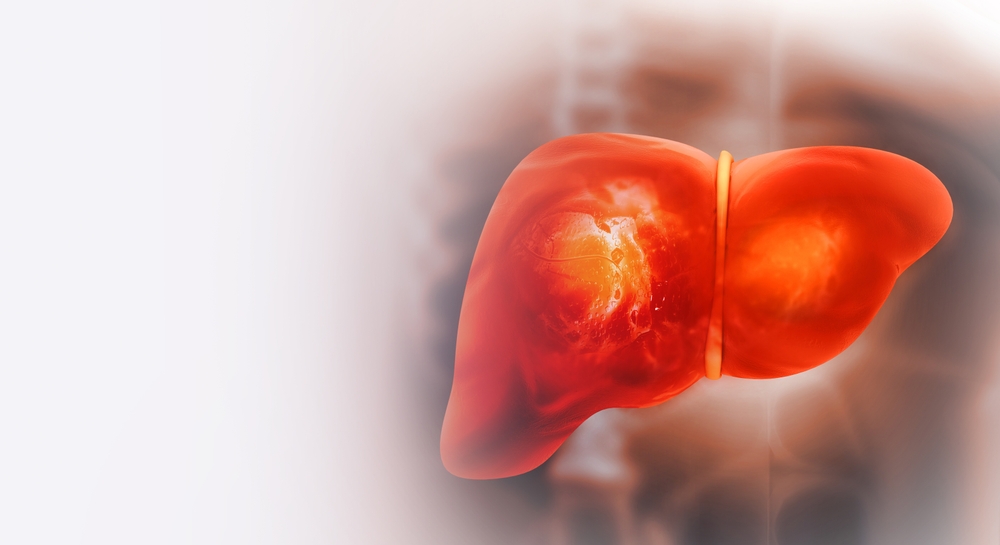

6 Warning Signs Your Liver is Full of Toxins – Don’t Ignore These Symptoms

Your liver is one of the most vital organs in your body. It filters the blood, breaks down toxins, processes nutrients, and aids digestion. When it becomes overwhelmed—whether...